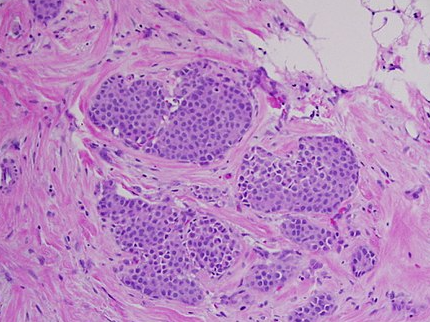

제자리암은 영어로 Carcinoma in situ라고 하며, 말 그대로 ‘제자리에 있는 암’을 의미합니다. 암세포가 생기긴 했지만, 기저막을 뚫지 않아 주변 조직으로 퍼지지 않은 상태를 말합니다. 이 단계에서는 세포가 비정상적으로 변했지만, 혈관이나 림프를 통해 다른 부위로 전이되지는 않습니다.

제자리암과 침윤암의 가장 큰 차이는 ‘퍼짐의 유무’입니다. 제자리암은 세포가 변형되었으나, 그 변화가 한정된 부위에 머무는 상태입니다. 반면 침윤암은 세포가 기저막을 넘어 주변 조직, 림프, 혈관 등으로 퍼진 상태를 말합니다. 따라서 침윤암은 수술, 항암, 방사선 치료 등 적극적 치료가 필요하지만, 제자리암은 비교적 관리 중심으로 접근할 수 있습니다.